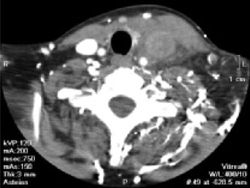

This particular presentation prompts you to order a computed tomography (CT) scan of her neck and chest, looking for a specific pathology (FIGURE 1).

When the scan is complete, the radiologist calls and confirms that there is occlusion of the left internal jugular vein, brachiocephalic vein, and a portion of the left subclavian vein with thrombosis.

The details. Thrombosis of the left internal jugular vein extends from the jugular siphon to the left subclavian vein. A portion of the left subclavian vein and probably the left brachiocephalic vein are also thrombosed. Numerous collaterals appear in the neck base. The left internal jugular vein measures 2.0 cm in diameter; the right measures 1.5 × 1.1 cm. There is also mild wall thickening of the internal jugular vein and infiltration of the surrounding fat—suggestive of septic thrombosis. No soft-tissue abscess is seen in the neck. The right internal jugular vein is normal. No definite thrombus is seen in the left jugular siphon or sigmoid sinus.

FIGURE 1 Thrombosed veins